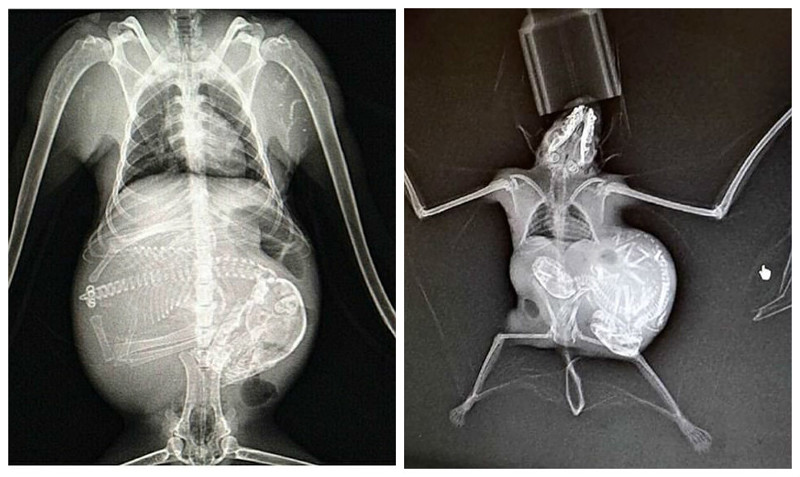

Как выглядит беременность животных на рентген-снимках (12 фото)

Представляем вашему вниманию серию интересных рентгеновских снимков, на которых можно рассмотреть, как располагаются будущие детеныши енота, летучей мыши или, скажем, бородатой ящерицы в животах их мам.

Енот

Летучая мышь